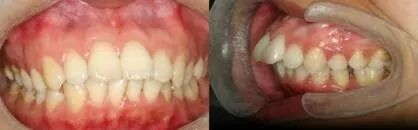

王某某,女,33岁,牙齿前突。上图是矫治前的牙齿图。

经过拔牙、戴金属牙套,1年半的牙齿矫正,前突的牙齿往回收了。

矫治前后脸型对比